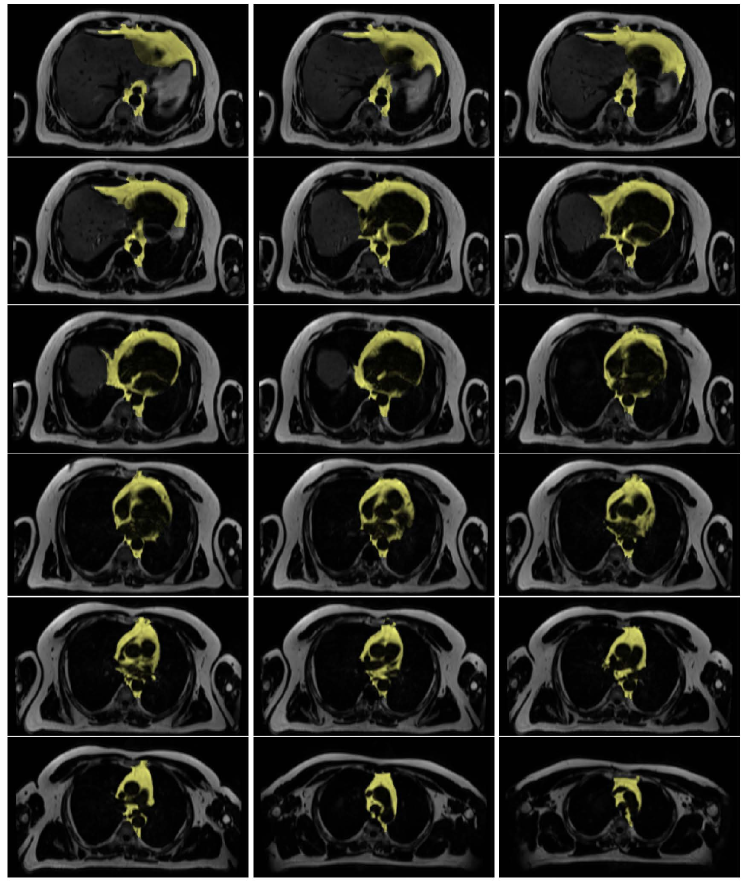

The classification priors of the samples could be estimated by any method such as the multiatlas registration or the hierarchical random forest classifier proposed in [Fallah 2018a, Fallah 2018b, Fallah 2019b, Fallah 2019a]. This happened when the classification probabilities estimated by those methods were not accurate enough to be considered as final classification probabilities (posteriors) rather as initial classification probabilities (priors). For example, the classification probabilities estimated by the proposed forest could not differentiate different kinds of cardiac adipose tissues on fat-water MR images. They could only differentiate the overall adipose tissues from nonadipose tissues. This was due to lack of spatial information in the forest, similar contrasts and features of the cardiac adipose tissues, and weak boundaries between them. The cardiac adipose tissues were spatially close to each other and separated only through thin septa which were hardly detectable under spatial resolution of standard clinical scanners at 3 T. Figure 1 shows voxelwise classification probabilities estimated by the proposed forest for the cardiac adipose tissues and the resulting segmentations on various slices of a fat image. Figure 2 shows overall segmentations of the cardiac adipose tissues based on the voxelwise classification probabilities estimated by the proposed forest on some axial slices of a fat image. Despite inaccuracies of the priors, they, features, and the spatial (neighborhood) relationships of the samples could pave the way for another classifier such as the neighborhood graph to classify the samples more accurately. For example, the priors could approximately localize an addressed object in an image and thereby speed up or reduce the complexity of its accurate segmentation. The more accurate classification probabilities were called the posteriors. Accordingly, the neighborhood graph was supposed to estimate the classification posteriors of every sample (vertex) with regard to its features, its priors, and its spatial (neighborhood) relationships with other samples of the same resolution .

The graphs proposed in section 3 and section 4 tried to implicitly or explicitly detect boundaries between different classes (e.g. objects) in spatial domain (e.g. image). The implicit boundary detection used the Tukey’s function of the features differences of the connected samples and the explicit boundary detection applied a 3D Sobel operator to each intensity channel of the samples. Both of these techniques could enhance the accuracies of a classification in spatial domain. However, their performance was limited when the features of different classes were similar or the boundaries were too weak to be detected. An example of these cases was segmentation of cardiac adipose tissues on fat-water MR images. As shown in Figure 1 and Figure 2 the random forest classifier proposed in [Fallah 2018a, Fallah 2018b, Fallah 2019b, Fallah 2019a] could only detect the overall adipose tissues but could not differentiate different kinds of it. The neighborhood graph proposed in section 3 or section 4 took the priors, the features, and the classification reliabilities of the samples and applied an implicit or explicit boundary detection. This could enhance the accuracy of the segmentation of the cardiac adipose tissues on fat-water MR images but the performance was still unsatisfactory. Figure 7 shows the voxelwise classification posteriors estimated for these adipose tissues by the implicit and/or explicit boundary detection on two axial slices of a fat image. To tackle features similarities and undetectable boundaries between different classes in spatial domain, we further extended the spatial feature-based subgraph by guiding the classification through additional information. These information got encoded into a diffusion-based susceptible-infected-recovered (SIR) model proposed in [Bampis 2017].